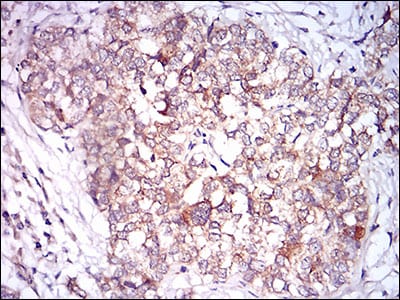

Immunohistochemical analysis of paraffin-embedded human prostate cancer tissues using CAMK2G mouse mAb with DAB staining.